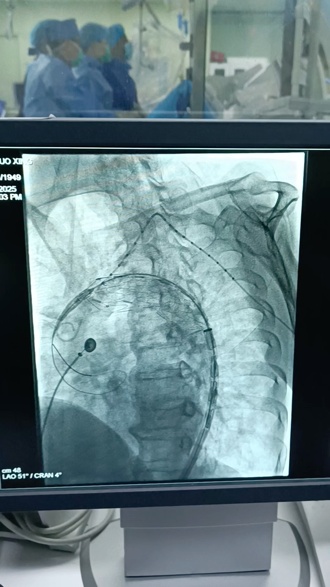

医院没有辜负患者和家属的期待。手术由血管外科与上海交通大学医学院附属第九人民医院血管外科主任陆信武团队的殷敏毅主任密切配合,采用尖端“锁骨下动脉激光开窗支架技术”。通过大腿股动脉植入定制的升主动脉覆膜支架,不仅精准封闭了动脉瘤,还保留了重要分支血管的血流。手术在DSA导管室进行,仅2小时后,这颗“不定时炸弹”被成功拆除,出血量仅20毫升。如今,蔡老伯恢复良好,已康复出院。